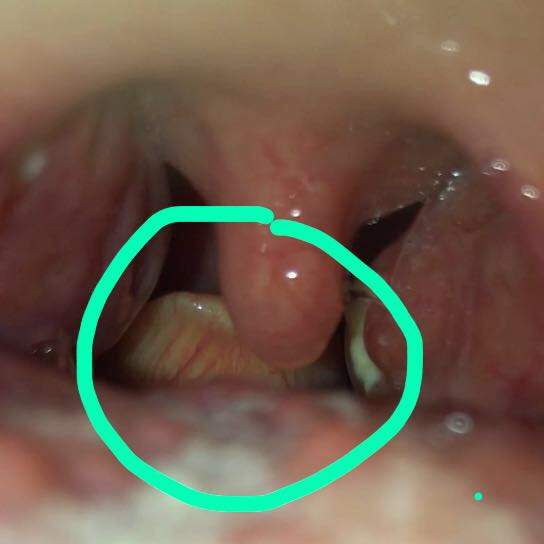

Ansonsten sind Mandelsteine harmlos nur selten führen größere Exemplare zu weiteren Beschwerden. Pickel im Rachen sind in der Regel ein Zeichen der Irritation. Mandelsteine Tonsillensteine sind weiß-gelbliche Gebilde die aus verschiedenen Substanzen in den Gaumenmandeln entstehen.

Ihr äußeres Erscheinungsbild einschließlich der Farbe hilft deinem Arzt die zugrunde liegende Ursache zu erkennen. Die Mandeln sind nur schwach gerötet und leicht geschwollen anfangs ist die Rachen- und Gaumenschleimhaut von weißlich-gelben Bläschen übersät.